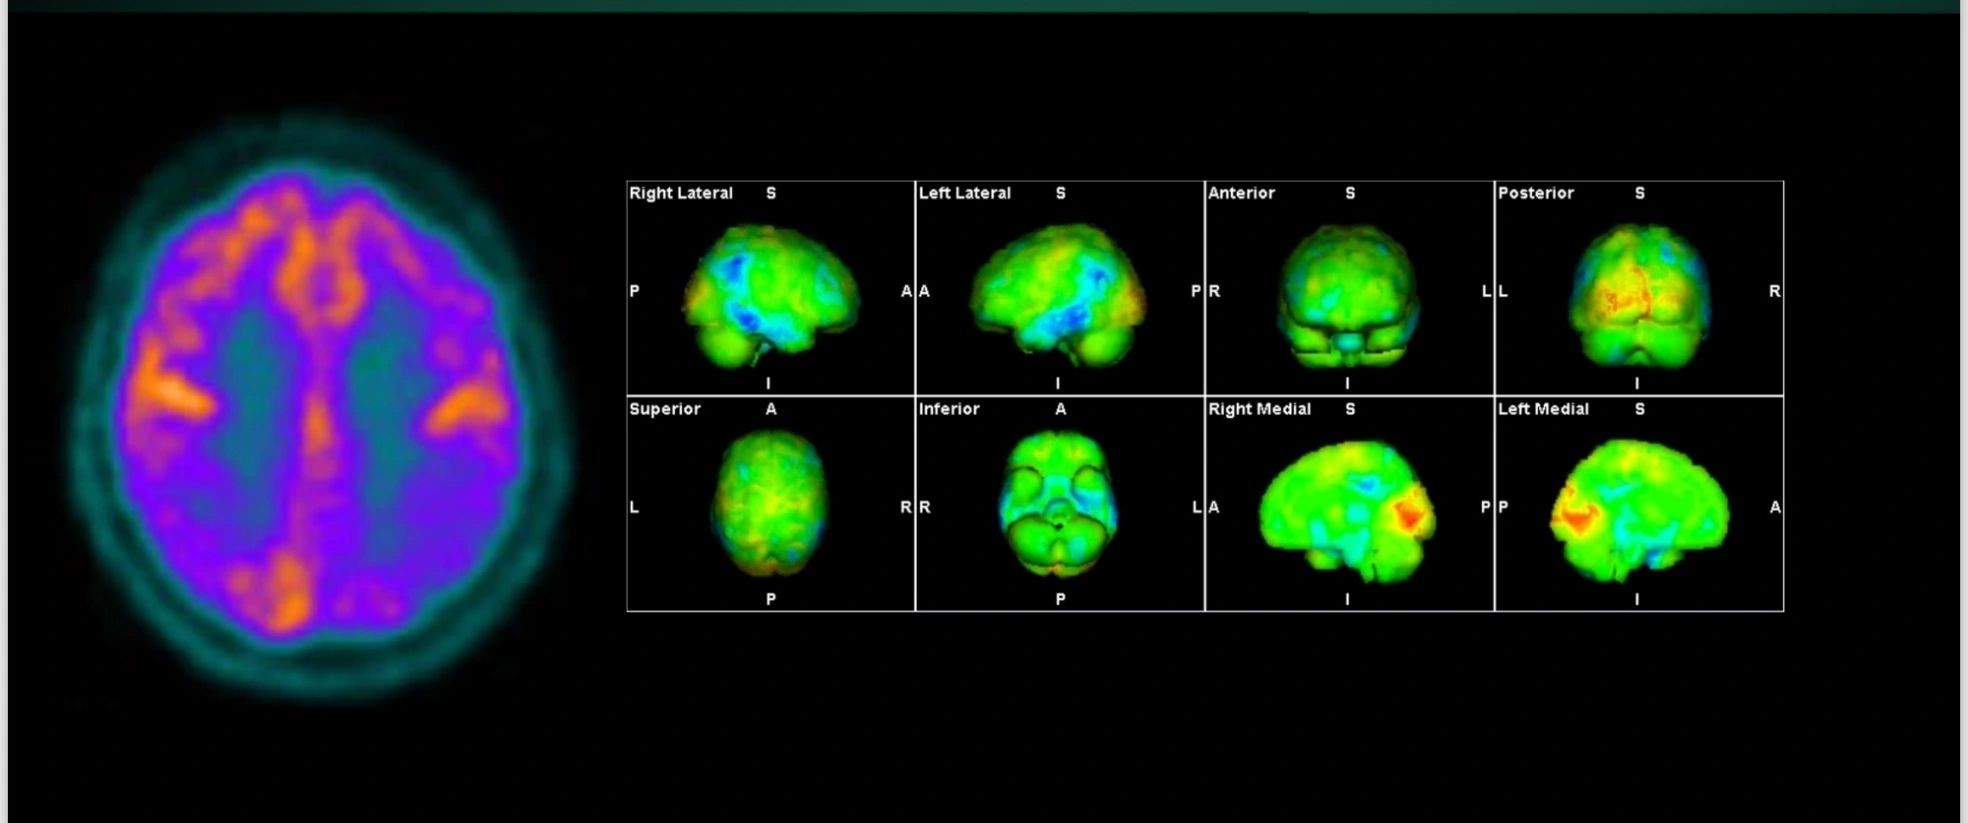

Η Τομογραφία Εκπομπής Ποζιτρονίων (PET) αποτελεί μια εξειδικευμένη μέθοδο της Πυρηνικής Ιατρικής που χρησιμοποιεί μοριακή απεικόνιση για να εντοπίσει και να παρακολουθήσει φυσιολογικές και παθολογικές λειτουργίες του οργανισμού. Συνδυάζοντας τη λειτουργική απεικόνιση της PET με την ανατομική πληροφορία της αξονικής τομογραφίας (CT), η υβριδική εξέταση PET/CT παρέχει εικόνες υψηλής ευκρίνειας και τη δυνατότητα ποσοτικής αξιολόγησης των βιολογικών μηχανισμών σε κυτταρικό επίπεδο.

Η PET/CT αποτελεί εξαιρετικά προηγμένη τεχνική της σύγχρονης ιατρικής απεικόνισης και χρησιμοποιείται τόσο για τη διάγνωση όσο και για την παρακολούθηση της ανταπόκρισης στη θεραπεία.

Οι κυριότερες εφαρμογές της αφορούν την ογκολογία, τη νευρολογία και, σε μικρότερο βαθμό, την καρδιολογία, ενώ συνεχώς αναπτύσσονται νέες χρήσεις σε άλλες ιατρικές ειδικότητες.

Με τη χρήση ειδικού λογισμικού Τεχνητής Νοημοσύνης (MIM – Lesion ID) πραγματοποιείται αυτόματος υπολογισμός της έκτασης και του όγκου των θέσεων ενεργού νόσου. Ξεπερνώντας τις δυνατότητες του ανθρώπινου οφθαλμού υπολογίζεται το συνολικό φορτίο νόσου πριν και μετά την θεραπεία επιτρέποντας ακριβέστερο χειρισμό του ασθενούς από τον θεράποντα ιατρό.